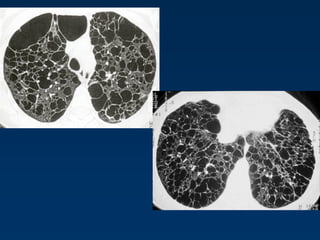

Panlobular emphysema

Affects the whole secondary lobule

Lower lobe predominance

In alpha-1-antitrypsin deficiency, but

also seen in smokers with advanced

emphysema

Affects the entire secondary pulmonary

lobule and is more pronounced in the lower

zones

Complete destruction of the entire pulmonary

lobule.

Results in an overall decrease in lung

attenuation and a reduction in size of

pulmonary vessels